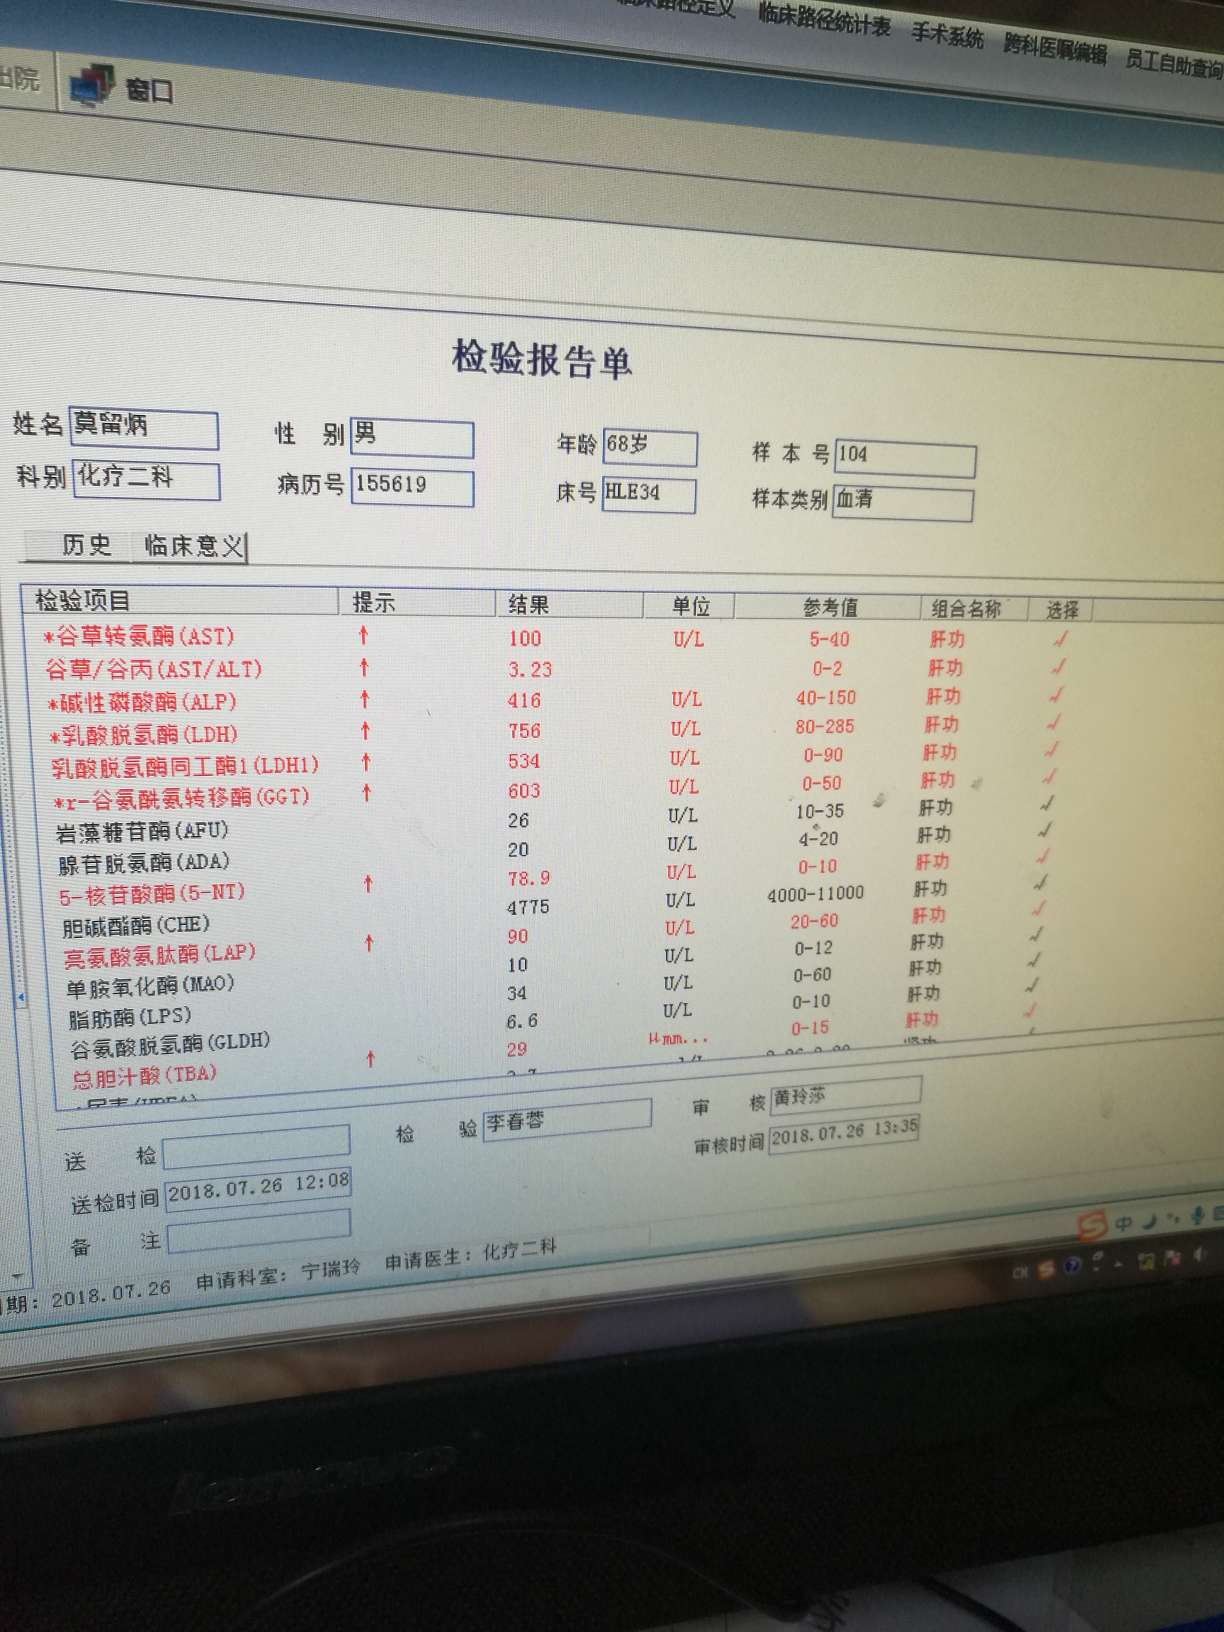

医生原来考虑用的治疗方案是美琣 卡鉑 恩度,但是现在考虑到我父亲的身体情况和肝损伤状况,决定化疗用美琣单药,3天后开始我父亲的第一次化疗。

想上免疫疗法,但是肝功能太差,需要把肝补好才能用K药。

肝部阴影多了很多,骨转,肾上腺都有,同时疑似有脑转,肿瘤标志物数值也升幅很大

肝部阴影多了很多,骨转,肾上腺都有,同时疑似有脑转,肿瘤标志物数值也升幅很大